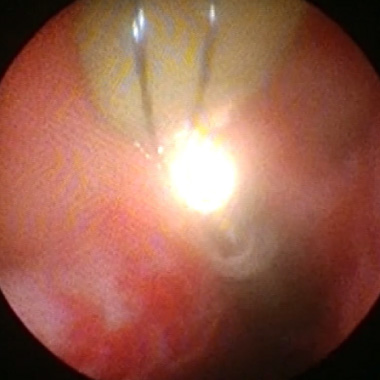

HoLEP

尿道を閉塞する前立腺腺腫

ホルミウムレーザーによる腺腫の核出(内腺のくり抜き)